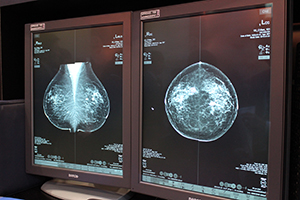

トモシンセシス撮影が可能なマンモグラフィシステム「Selenia Dimensions」は,昨2013年末にリリースされたトモシンセシス(3D)画像から2D画像を生成する“C-View”や,3D画像により位置決めを行うTomoBiopsyがITEMでは初めての展示となった。

「Selenia Dimensions」の新機能“C-View” |